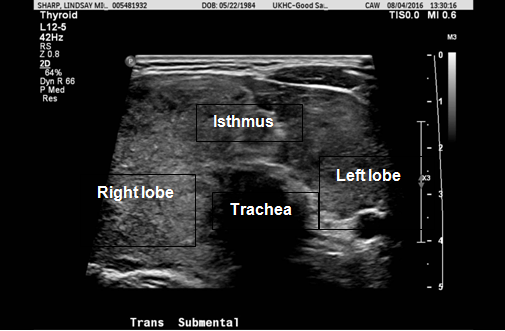

A 32-year-old female with a history of Hodgkin’s lymphoma presented with a two week history of thyromegaly. Hodgkin’s lymphoma was diagnosed at the age of 29 years and was treated with two cycles of ABVD (doxorubicin, bleomycin, vinblastine, and dacarbazine) chemotherapy and radiation therapy which was 2000 cGy in 10 fractions to the left lower cervical and supraclavicular nodal regions. One year after her diagnosis of lymphoma, she was considered to be in remission. She was also diagnosed with hypothyroidism with elevated anti-thyroid peroxidase antibody levels at the age of 29 years and treated with levothyroxine. At the age of 32 years , she developed thyromegaly causing dysphagia and hoarseness over a two-week interval. Physical examination revealed thyromegaly but no cervical lymphadenopathy. Due to her history of lymphoma positron emission tomography (PET) imaging was performed and demonstrated increased, diffuse fluorodeoxyglucose (FDG) uptake in the thyroid with right lobe being larger than the left (Figure 1). Ultrasound was also performed and showed thyromegaly especially on the right side but no thyroid nodules (Figure 2). Fine needle aspiration (FNA) of the right lobe was performed with flow cytometry of the needle washings (Figure 3). Flow cytometry of the needle washings did not show any clonal or aberrant populations of lymphocytes making lymphoma unlikely. Cytologic examination showed a background of lymphocytes and lymphoid stroma consistent with Hashimoto’s thyroiditis. Over the next two months the patient’s thyromegaly, dysphagia, and hoarseness gradually resolved. She continued to be treated with levothyroxine for her hypothyroidism related to Hashimoto’s thyroiditis.

Figure 3: Transverse ultrasound image demonstrating needle during fine needle aspiration of thyroid. The needle and right lobe have been labeled.

Hashimoto’s thyroiditis may result in acute thyromegaly and increased fluorodeoxyglucose uptake on positron emission tomography imaging which may mimic the presentation of lymphoma of the thyroid. Fine needle aspiration of the thyroid with flow cytometry of needle washings can be used to distinguish lymphoma of the thyroid from Hashimoto’s thyroiditis.